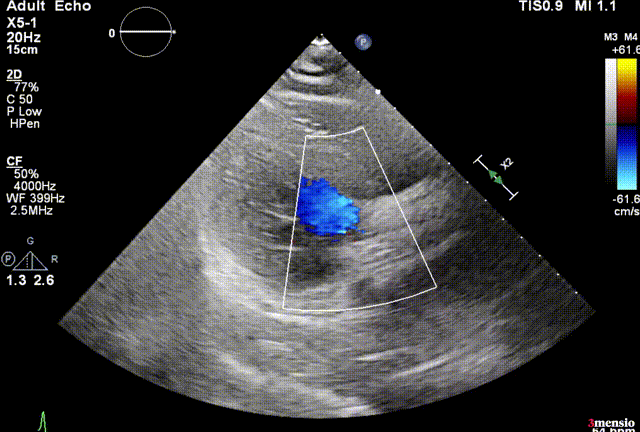

患者:女性,74岁,因“活动后胸闷气急1年”入院,超声心动图提示:主动脉瓣口流速6.42 m/s,平均跨瓣压差100mmHg,LVEF66.6%,主动脉瓣钙化并重度狭窄,升主动脉狭窄后扩张,主动脉弓部增宽,二尖瓣中等量反流。

超声提示微量瓣周漏,瓣膜工作良好,最大跨瓣流速2.02m/s,平均压差6mmHg。